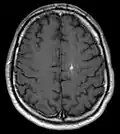

Diagnosis is generally made by magnetic resonance imaging (MRI), particularly using a specific imaging technique known as a gradient-echo sequence MRI, which can unmask small or punctate lesions that may otherwise remain undetected. These lesions are also more conspicuous on FLAIR imaging compared to standard T2 weighing. FLAIR imaging is different from gradient sequences. Rather, it is similar to T2 weighing but suppresses free-flowing fluid signal. Sometimes quiescent CCMs can be revealed as incidental findings during MRI exams ordered for other reasons. Many cavernous hemangiomas are detected "accidentally" during MRIs searching for other pathologies. These "incidentalomas" are generally asymptomatic. In the case of hemorrhage, however, a CT scan is more efficient at showing new blood than an MRI, and when brain hemorrhage is suspected, a CT scan may be ordered first, followed by an MRI to confirm the type of lesion that has bled.[19] Sometimes the lesion appearance imaged by MRI remains inconclusive. Consequently, neurosurgeons will order a cerebral angiogram or magnetic resonance angiogram. Since CCMs are low flow lesions (they are hooked into the venous side of the circulatory system), they will be angiographically occult (invisible). If a lesion is discernible via angiogram in the same location as in the MRI, then an arteriovenous malformation (AVM) becomes the primary concern.